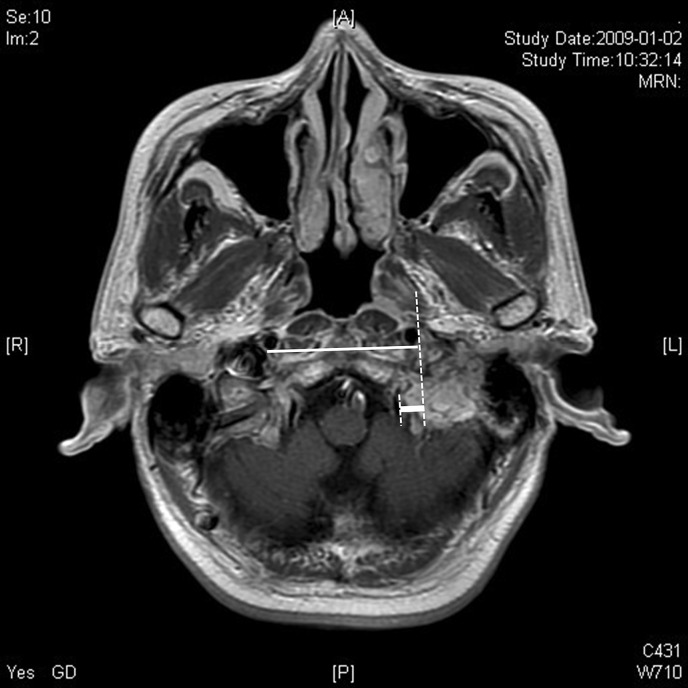

Results: The study included 19 patients with a mean age of 43.1 years (standard deviation [SD], 16.1 years). The average tumor size was 28.6 mm (SD 12.6 mm). In patients with Fisch classes C1 and C2 tumors, there were 3 and 11 patients, respectively. Gross total tumor removal (GTR) was performed in all patients with classes C1 and C2. GTR was achieved in 2 out of the 5 patients with class C3 tumor. Seventeen patients underwent ITFA-A and 2 patients underwent partial rerouting. Facial function before surgery was normal in all but 3 cases. Among 16 patients with preoperative normal facial function, 13 had H-B grade I to II and 3 had H-B grade III at 1 year after surgery. Total and partial rerouting did not significantly affect facial function immediately after surgery or at the postoperative 1-year evaluation (p = 1.00). Preoperative LCN function was normal in all patients. LCN palsy lasting more than 1 year occurred in 7 patients after surgery. Patients with Fisch class C1 tumor did not develop postoperative LCN palsy. Among the patients with class C2 tumor, none of 5 patients with medial invasion depth less than 9.5 mm developed LCN palsy, whereas 5 of 6 patients (83.3%) with invasion depth of 9.5 mm or greater developed LCN palsy (p = 0.02).

简介壶腹部副神经节瘤(Jugulotympanic paraganglioma,JTP)是指发生于壶腹部的副神经节瘤,可侵犯骨骼、血管、脑膜和颅神经等周围结构。作者开展了一项研究,通过分析接受 JTP 手术治疗的患者病历,寻找手术适应症,以避免严重的颅神经并发症:我们对2004年至2022年期间接受JTP切除术的患者进行了单机构回顾性研究。患者接受了Fisch颞下窝入路A型(ITFA-A)或改良ITFA-A并部分改道面神经的手术。对术前、术后下颅神经(LCN)功能和面部功能进行了评估(采用 House-Brackmann (H-B) 分级):研究共纳入 19 名患者,平均年龄为 43.1 岁(标准差(SD)为 16.1 岁)。肿瘤平均大小为 28.6 毫米(标准差为 12.6 毫米)。费希C1级和C2级肿瘤患者分别有3人和11人。所有C1级和C2级患者都进行了肿瘤全切(GTR)。在 5 名 C3 级肿瘤患者中,有 2 人实现了肿瘤全切。17名患者接受了ITFA-A手术,2名患者接受了部分改道手术。除 3 例患者外,其他患者术前面部功能均正常。术前面部功能正常的 16 例患者中,13 例在术后 1 年达到 H-B I 至 II 级,3 例达到 H-B III 级。全部和部分改道对术后即刻或术后 1 年评估时的面部功能没有明显影响(P = 1.00)。所有患者术前的 LCN 功能均正常。7 名患者术后出现了持续 1 年以上的 LCN 麻痹。Fisch C1级肿瘤患者术后未出现LCN麻痹。在C2级肿瘤患者中,内侧侵犯深度小于9.5毫米的5名患者无一出现LCN麻痹,而侵犯深度大于或等于9.5毫米的6名患者中有5名(83.3%)出现LCN麻痹(P = 0.02):结论:内侧深度侵犯的 JTP 应采取保守治疗,以防止 LCN 麻痹。